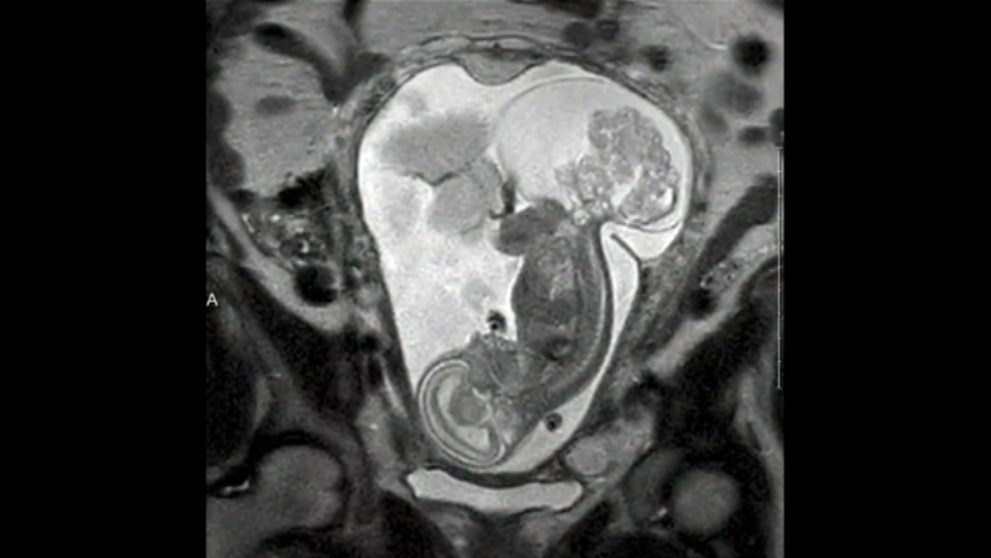

Dievčatko sa narodilo dvakrát. Lekári zistili matke v 16. týždni tehotenstva pri rutinnom ultrazvuku, že na plode je tumor. Nádor rástol a dieťa by skôr či neskôr zabil.

„Bolo to veľmi ľahké rozhodovanie. Chceli sme jej dať šancu na život," povedala matka pre denník DailyMail. Operáciu podstúpila v 24. týždni tehotenstva. Nádor bol v tom čase takmer rovnako veľký ako dieťa. Zákrok trval 5 hodín a dieťa bolo mimo tela matky 20 minút.

Po úspešnej operácii dieťa vložili naspäť do matkinej maternice a tú zašili. Dievčatko sa narodilo 12 týždňov po zákroku, keď matka bola 36. týždni cisárskym rezom. Po narodení vážila 2, 5 kg.